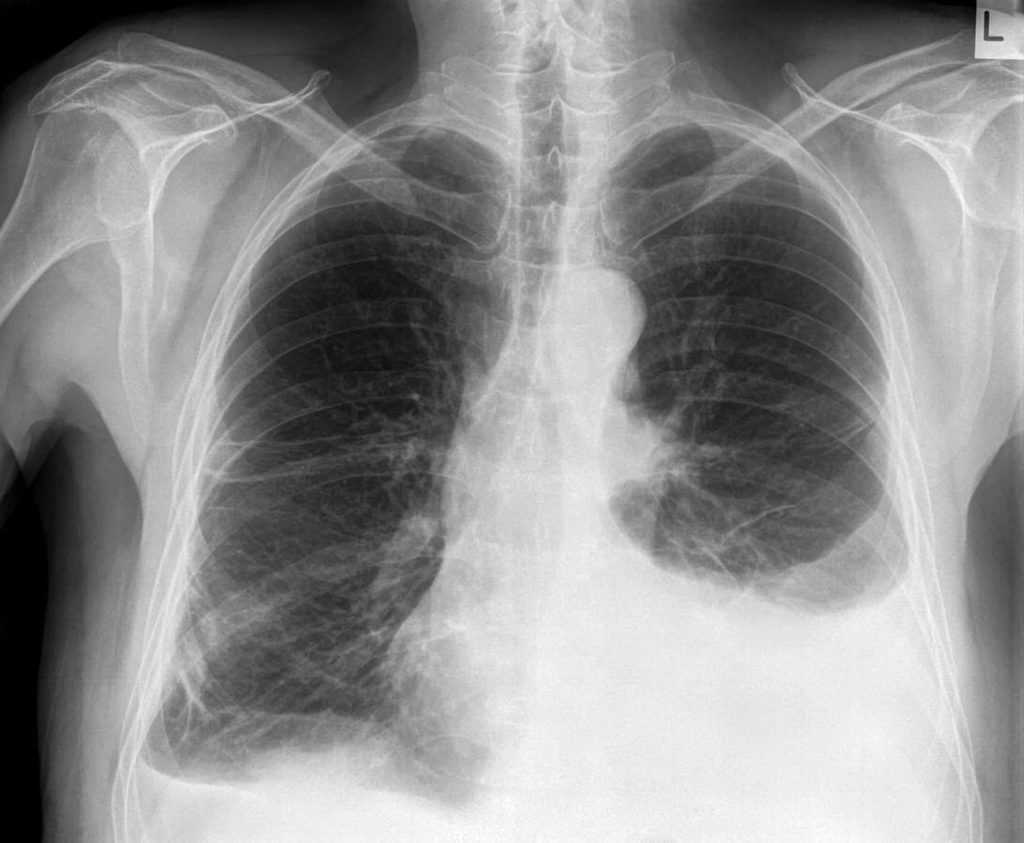

Ателектаз на рентгене

Обзор

Рентгенологическое исследование может помочь в диагностике ателектаза. Рентгенологические данные, свидетельствующие об ателектазе, включают смещение фиссур, скученность ребер, подъем ипсилатеральной диафрагмы, потерю объема на ипсилатеральном полутораксе, смещение ворот и компенсаторную гиперпрозрачность остальных долей.![]()

- Ателектаз легкого — очень частая аномалия, выявляемая на рентгенограммах органов грудной клетки. Аномалии на рентгенограмме грудной клетки из-за ателектаза помогают определить основную патологию.

- Различные типы ателектазов имеют свою характерную рентгенологическую картину и этиологию.